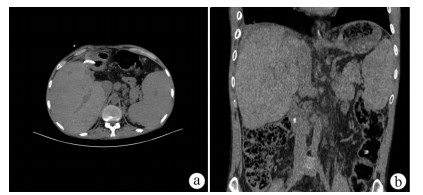

Intraductal papillary neoplasm of the bile duct with atrophy of the hepatic left lateral lobe: A case report

Jingzhong OUYANG, Ruili ZHU, Yanzhao ZHOU, Zhengzheng WANG, Xun CHEN, Jinxue ZHOU, Qingjun LI

2021, 37(7): 1676-1678. DOI: 10.3969/j.issn.1001-5256.2021.07.041

Abstract(772) HTML (338) PDF (2403KB)(24)

Abstract: